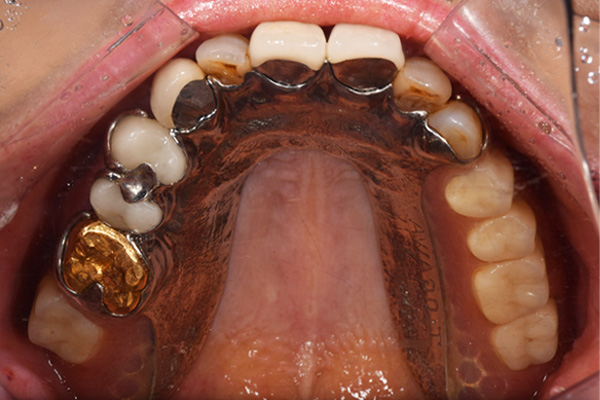

右上と左下の歯がない方です。 上の入れ歯の安定が悪く、作り直したいとのことでいらっしゃいました。 今お使いの上の入れ歯を見てみると、口蓋部分が抜けており、安定性に欠ける構造になっていました。この入れ歯はノンメタルクラスプデンチャーといって、金属のバネを使用しない 入れ歯になります。これは見た目は良いのですが、歯への負担が大きいことと、入れ歯自体がやわらかいため、噛むには不便なことがあります。

入れ歯は極力薄くするために金属を使用しました。しっかり噛める様にするため、ノンメタルクラスプデンチャーにはしませんでした。

上の入れ歯(表)

上の入れ歯(裏)

下の入れ歯

入れ歯を入れた状態のお口の中の写真です。バネも極力目立たないように作成しています。

こちらが完成したかぶせ物と入れ歯です。かぶせ物にはアタッチメントをつけて金属のバネが見えない構造になっています。 入れ歯自体も金属を使用して、極力違和感がでないように、薄く作成しました。